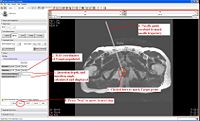

PerkStationModule.JPG

Hardware/software overlay for percutaneous intervention (PERK Station)

The Queen’s/Hopkins team is developing novel devices and procedures for cancer interventions, including biopsy and therapies. This particular project involves design and development of a hardware/software system that can be used in either clinical mode to perform an intervention or in training mode to objectively evaluate the performance of trainee doing a percutaneous needle intervention on a phantom. More...